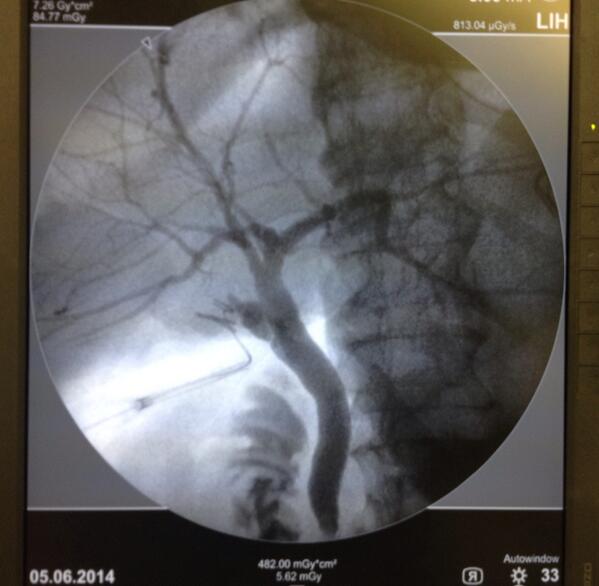

UVB HUCC3: Colelap+CIO en pte Post-CPRE fallida @liuma2000 @mafevisconti @CIMHUC @omaale7 @metalandros @drSanchezA